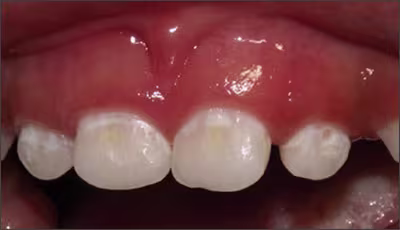

It develops in smooth surfaces and progresses rapidly. There is usually a pattern seen in this disease in which affects – maxillary anterior→maxillary and mandibular first primary molars→mandibular canines.12 It can be considered a particularly virulent form of caries.The mandibular incisors are usually unaffected.12

Figure 7. Initial white decalcification of the anterior teeth and incipient caries lesion.

Image courtesy of Norman Tinanoff, DDS, MS.